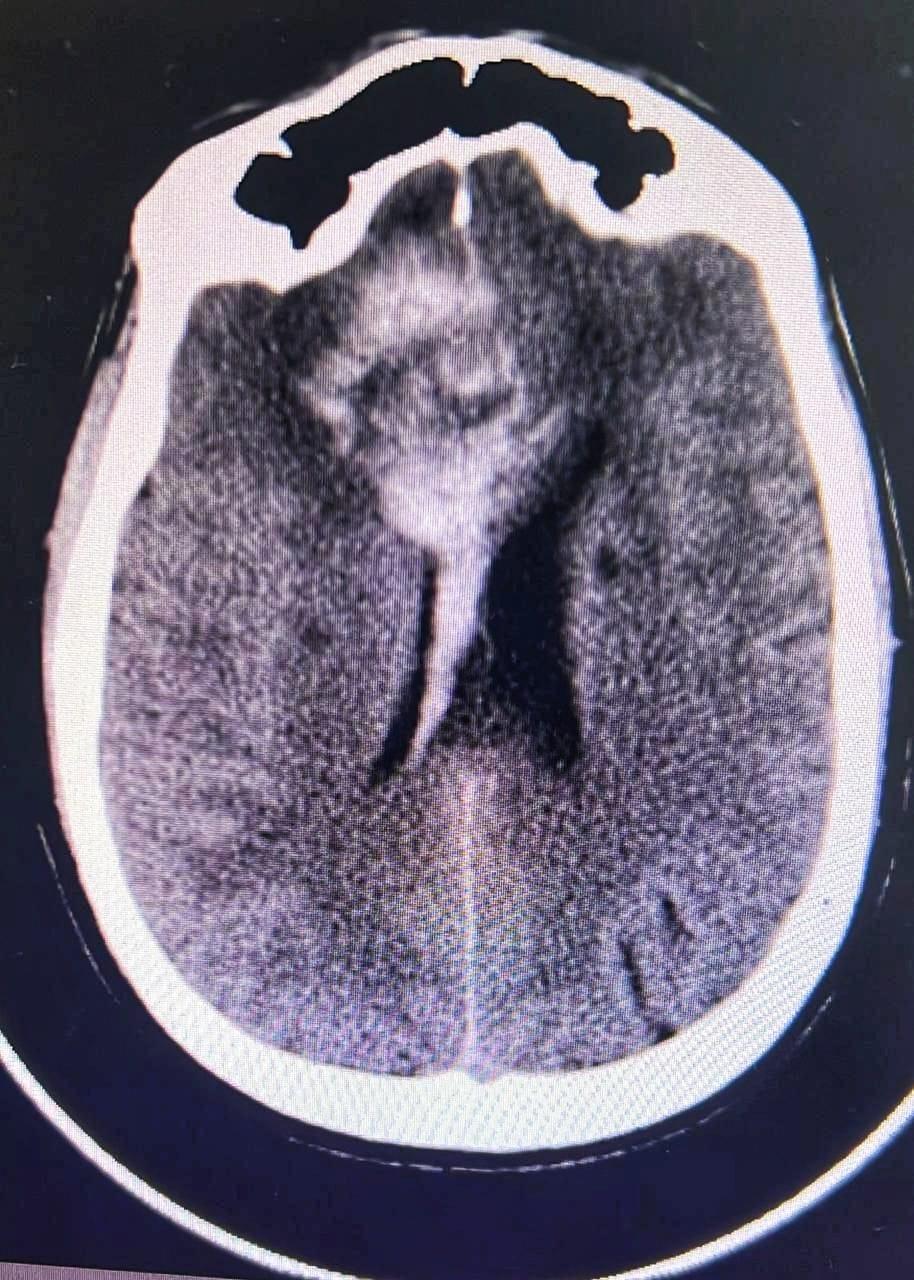

وتم اجراء الفحوصات اللازمة له وتبين وجود تمدد في الأوعية الدموية في الفص الأيسر من الدماغ مسببا انفجار الشريان الوسطي الدماغي الأيسر.

وأوضح الدكتور أنور الهاشم رئيس قسم جراحة المخ والأعصاب والعمود الفقري ان الفحوصات أظهرت تلفا في مركز الحركة في الفص الأيسر ونقصا في التروية الدموية مهددا بفقدان وظائف هذا الفص بشكل شبه دائم.